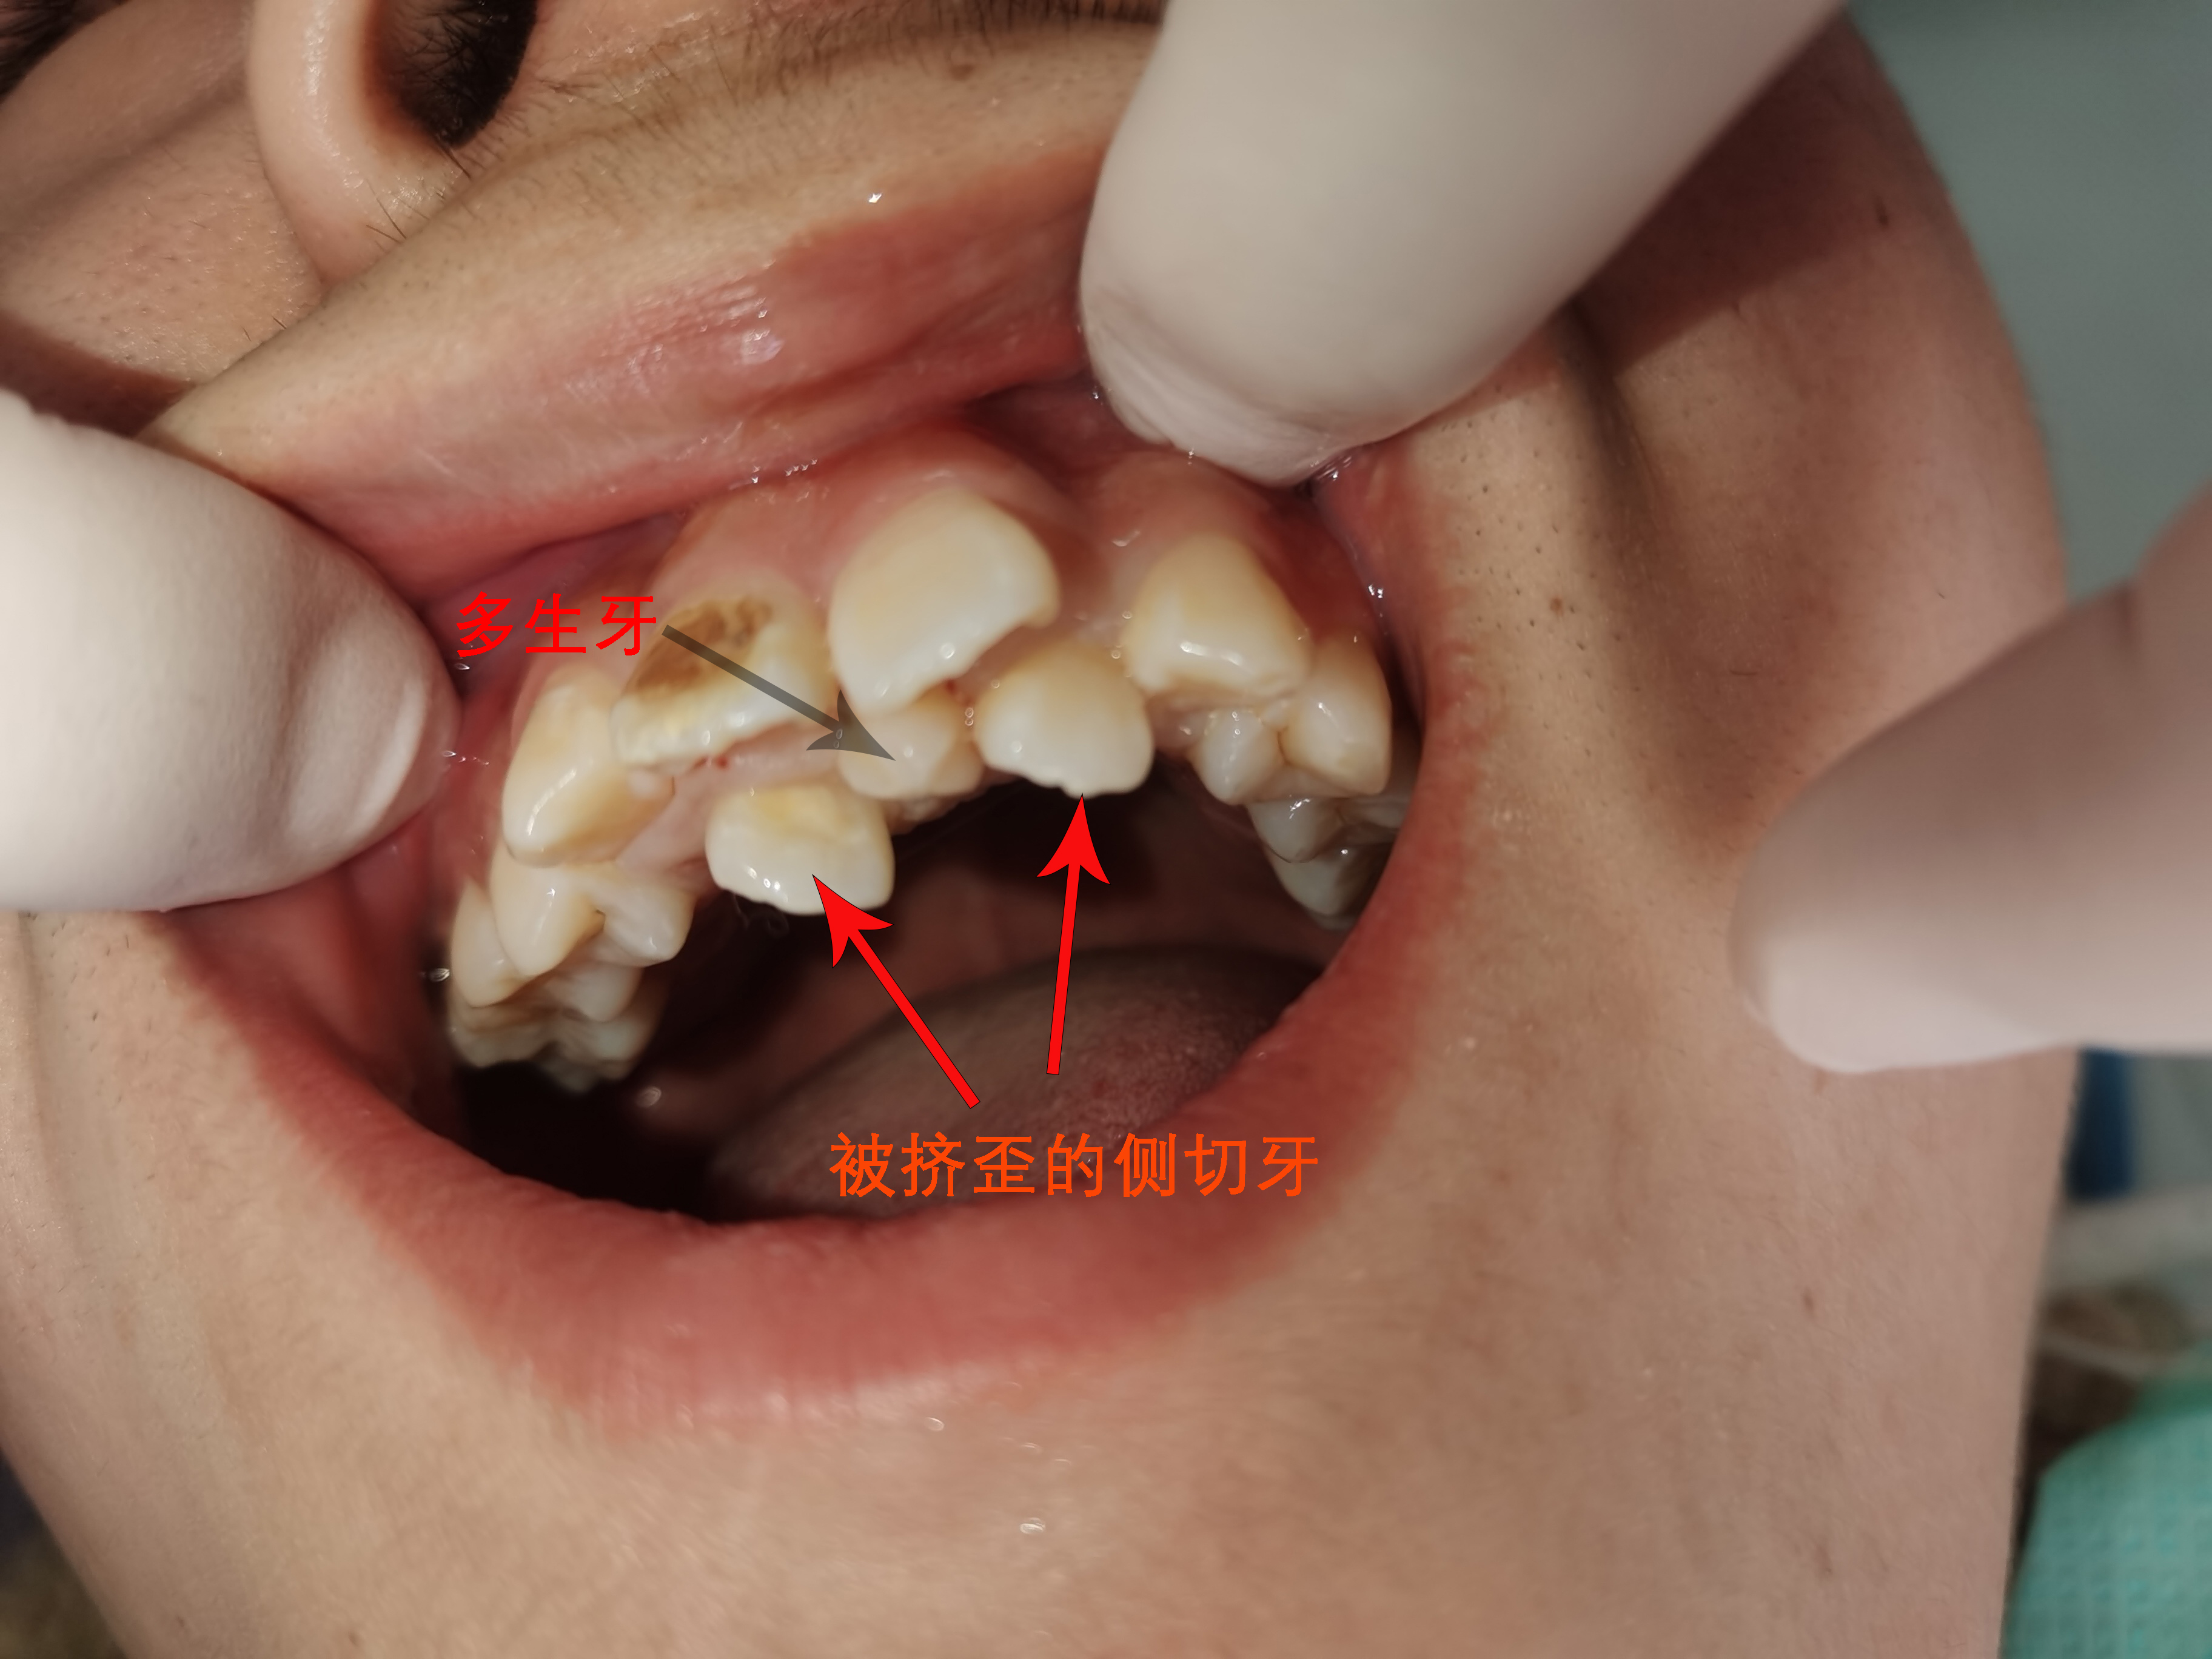

多生牙严重影响临近正常牙的萌出

近日,25岁的小李来到捷克论坛 口腔二科就诊,要求拔除口腔内怪异的牙齿,说严重影响到美观和口腔功能。接诊医生余顺医师仔细检查小李口腔内情况,发现他上颌牙齿非常不整齐,两颗大门牙尚在正常的位置,旁边的两颗侧切牙却偏离到牙列内侧很远的地方,而在四颗门牙的正中间还嵌着一颗形状怪异的畸形牙。

余顺医师为小李解释,上前牙列不齐是因为中间那颗畸形多生牙导致的,在乳牙换恒牙阶段,因为中间多生牙的阻挡,导致旁边两颗侧切牙不能萌出到正常位置,被排挤到了牙列之外。小李表示,其实小时候在当地牙科诊所就发现了多生牙,但当时医生给出的建议是暂时先不处理,没有技术拔除多生牙,怕损伤到恒牙。结果等长大后牙齿越来越不齐,多生牙也一直还在,现在非常影响美观了,才想起来医院看牙。